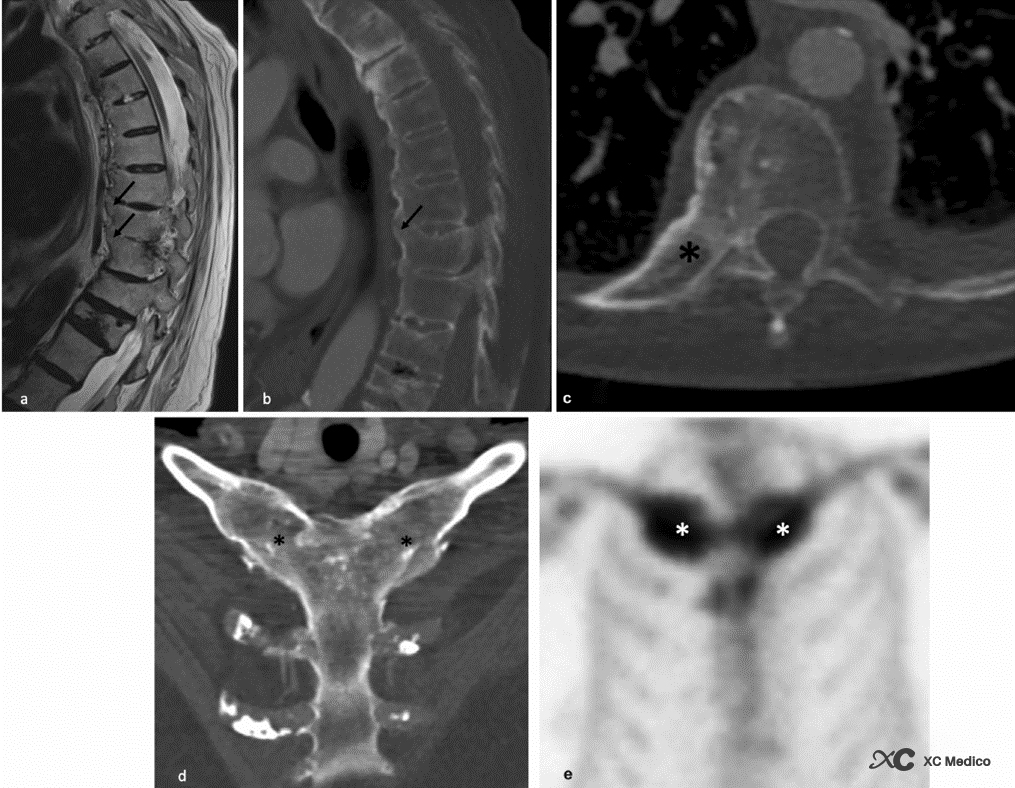

Примечание: 62-летний мужчина с синдромом Сэфо. (A) Сэгиттальные T2-взвешенные и (б) изображения компьютерной томографии (КТ) показывают окостенение передней продольной связки (черные стрелки) нет существенных нарушений диска или паравертебральной жидкости. L1 сильно перемещается после старого перелома сжатия. (C) Осевая КТ показывает анкилоз правильного затратковообразного сустава (звездочка). (D) Наклонная корональная КТ -реконструкция показывает двустороннюю кнопку грудной клетки, анкилоз (черные звездочки). (e) Сканирование костей, показывающее поглощение радиоотранслятора в обоих пораженных суставах (белые звездочки).